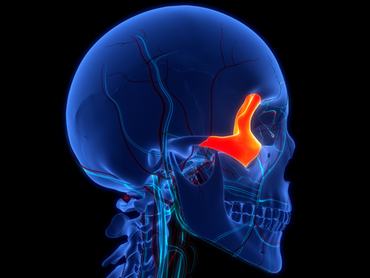

6. kérdés

Melyik csont látható kiemelve a képen?

halántékcsont

járomcsont

hallócsont